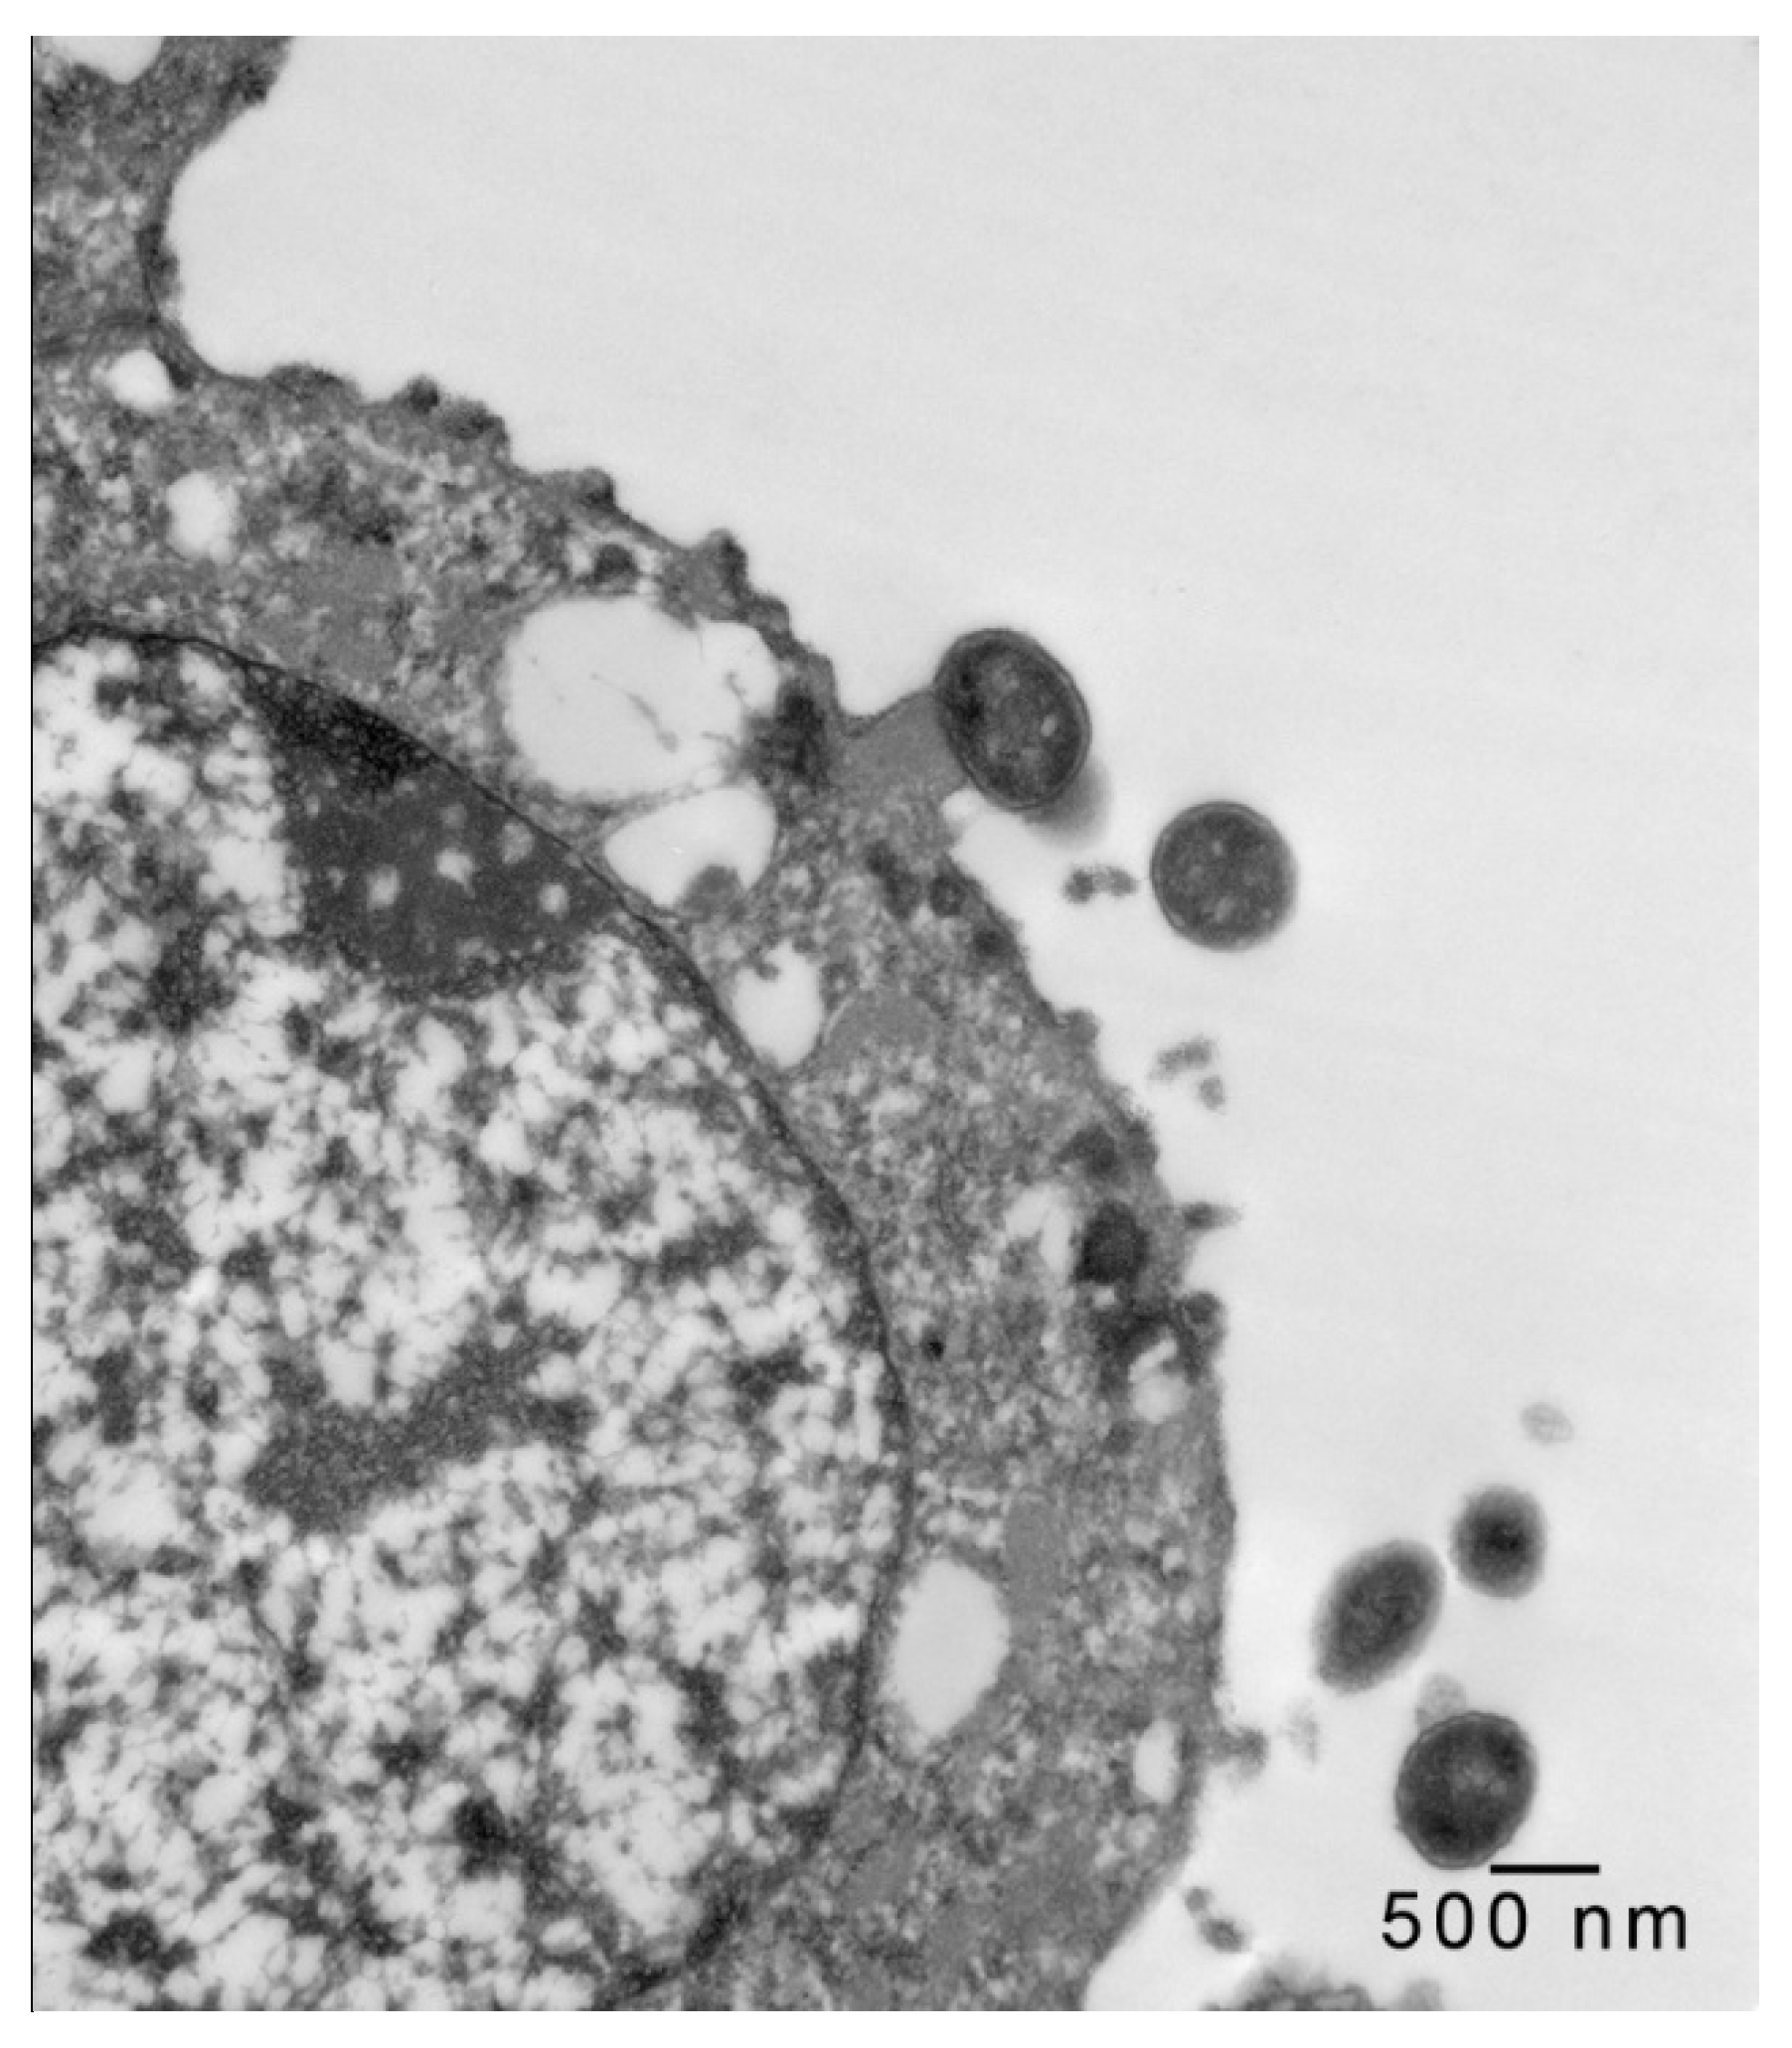

In 1-μm thick Araldite sections of urinary bladder prepared from tissues originally contained within the paraffin blocks [25], bacteria were detected only in piglet 15627 (Figure 1). In this piglet, in which bladder sections were oriented such that all three cell layers (basal, intermediate and superficial or umbrella) of the urothelium [26,27,28,29] were visible, bacteria, corresponding to bovine-origin strain 2891, were diffusely adherent to the apical surfaces of umbrella cells. By TEM, bacterial cells were found intimately attached to pedestals (Figure 2, Figure 3 and Figure 4). Some bacterial cells appeared to be attached to microplicae, preceding pedestal formation (Figure 4).

Figure 4.

Transmission electron photomicrograph of a thin section of a superficial epithelial (umbrella) cell of the urinary bladder of piglet 15627, 8 days PI with bovine-origin strain 2891. This field shows more extensive colonization, with bacteria attached to pedestals and apparent early attachment to microplicae (arrows). Bar = 500 nm.

Morphologically, the pedestals to which bacteria in the urinary bladder of piglet 15627 were intimately attached were consistent with actin pedestals induced by EHEC and enteropathogenic E. coli (EPEC) in intestinal epithelium [24]. To our knowledge, this is the first report of intimate bacterial adherence and actin pedestals in the uroepithelium in any species. Staley et al. [30] first reported these lesions in 1969, describing them as attachment and microvillous exfoliation in ileal enterocytes of newborn, cesarean-derived piglets intragastrically inoculated with an E. coli strain belonging to a classical EPEC serotype, O55:H7. Takeuchi et al. [31] later described these lesions as occurring in rabbits inoculated with RDEC-1, a rabbit-origin O15:NM E. coli later classified as an EPEC [23]. Soon thereafter, the lesions were recognized in human infants with EPEC infection [32,33]. Moon et al. coined the term “attaching and effacing” to describe intimate attachment and effacement of microvilli in the intestinal epithelium of piglets and rabbits by EPEC [23]. Knutton et al. [34] first determined that the electron-dense material underlying the bacteria within the pedestals was filamentous actin. Over the past 50 years since the initial report by Staley et al. [30], numerous studies, many at the molecular level, have elucidated key bacterial and host factors involved in the pathogenesis of intimate attachment and pedestal formation [29].